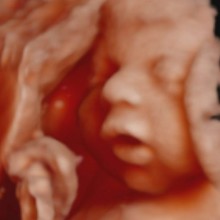

Veja o seu bebé projetado diretamente na sua barriga e desfrute da melhor imagem pré natal 5D com fotos, vídeo incluído e batimento cardíaco do bebé.

Esta sessão inclui 1 foto 8K que é a imagem o mais aproximado possível da realidade do seu bebé.

1 foto 8K (idealmente a partir das 26 semanas de gestação)